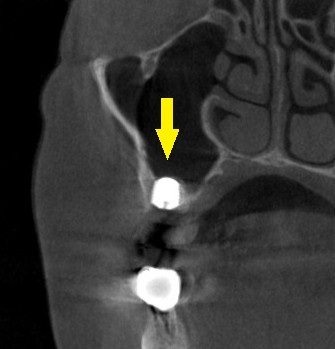

CTを撮影してみると、骨の高さが3mm程しかありませんでした。

下の写真、2段目が手術前、3段目が手術後のCTです。